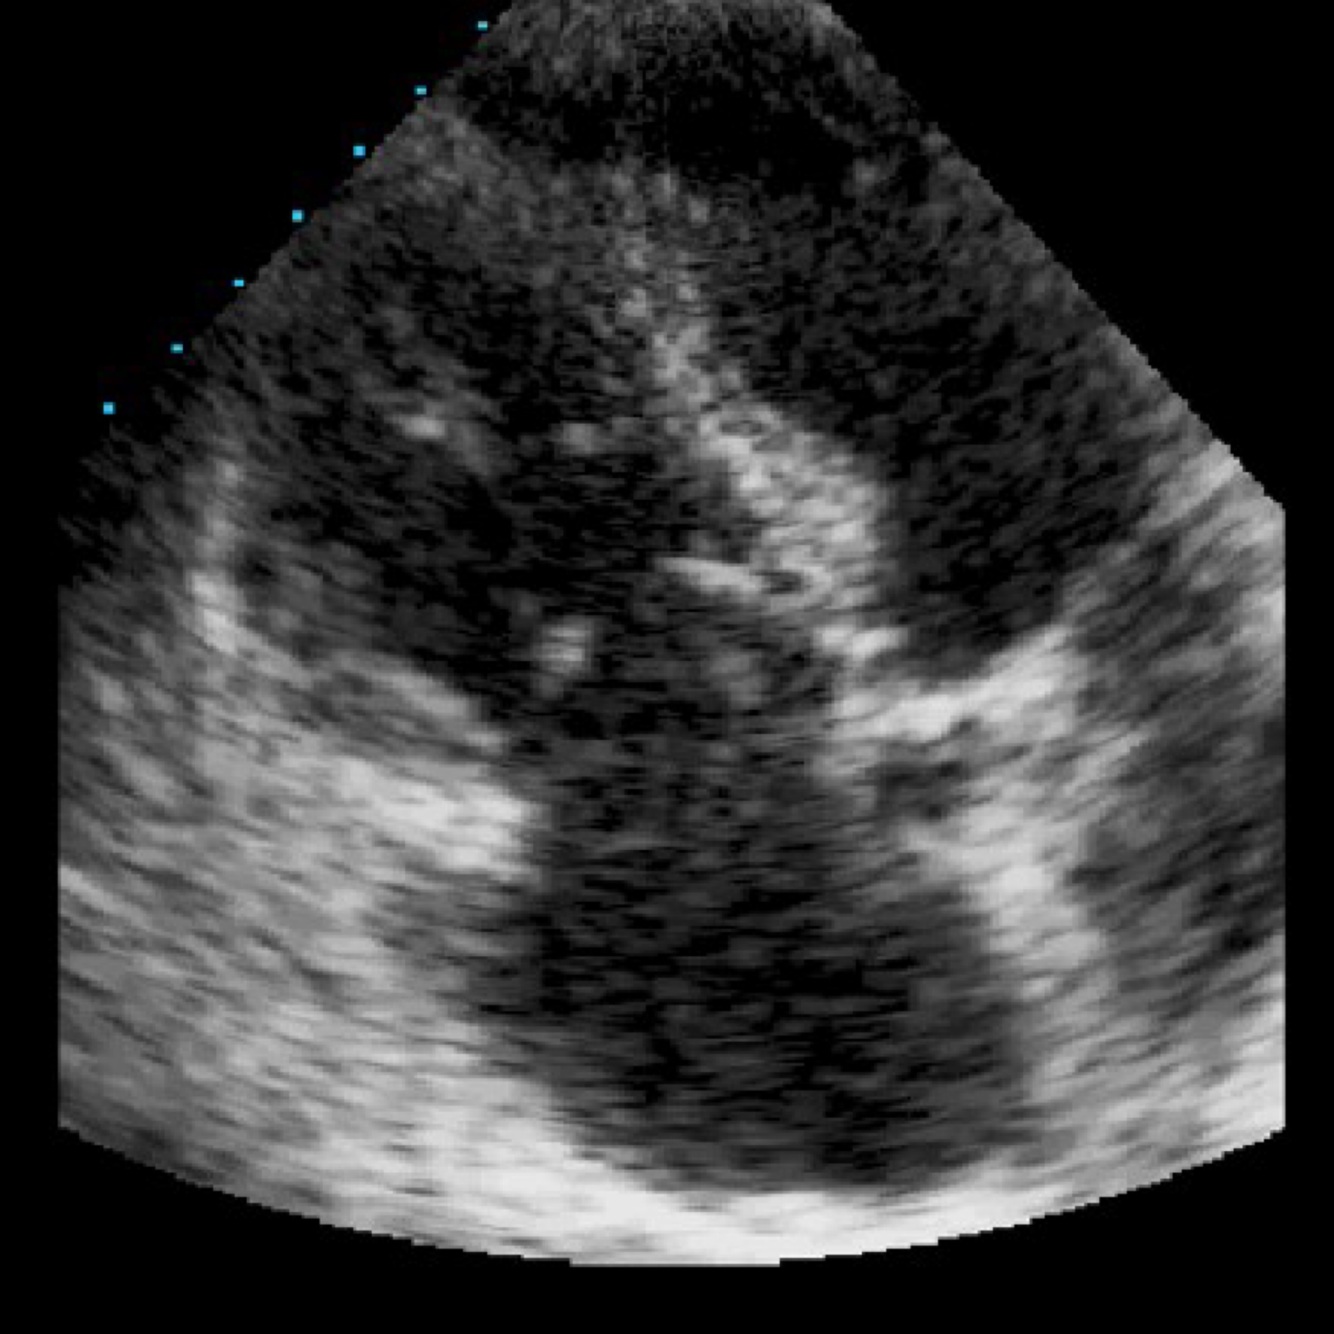

Your patients TV is shown here during systole. The Mitral valve appears normal. What is the most likely pathology shown?

A

Carcinoid TV

Carcinoid heart affects RT heart, particularly the TV. It causes the valve to become retracted and immobile. Rheumatic TV has a similar appearance, but would also affect the MV.